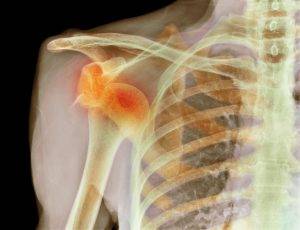

На этих фото показано, какие кости относятся к скелету пояса верхней конечности:

Основные движения в сочленении плеча выполняются при помощи головки, расположенной в глубине лопаточной кости. Плечевой сустав испытывает большие нагрузки. Из-за этого воспаление и структурный износ кости – явление достаточно частое. Для установления диагноза врач может направить на проведение рентгеновского исследования. Полученное при этом фото позволит максимально точно оценить состояние сустава.